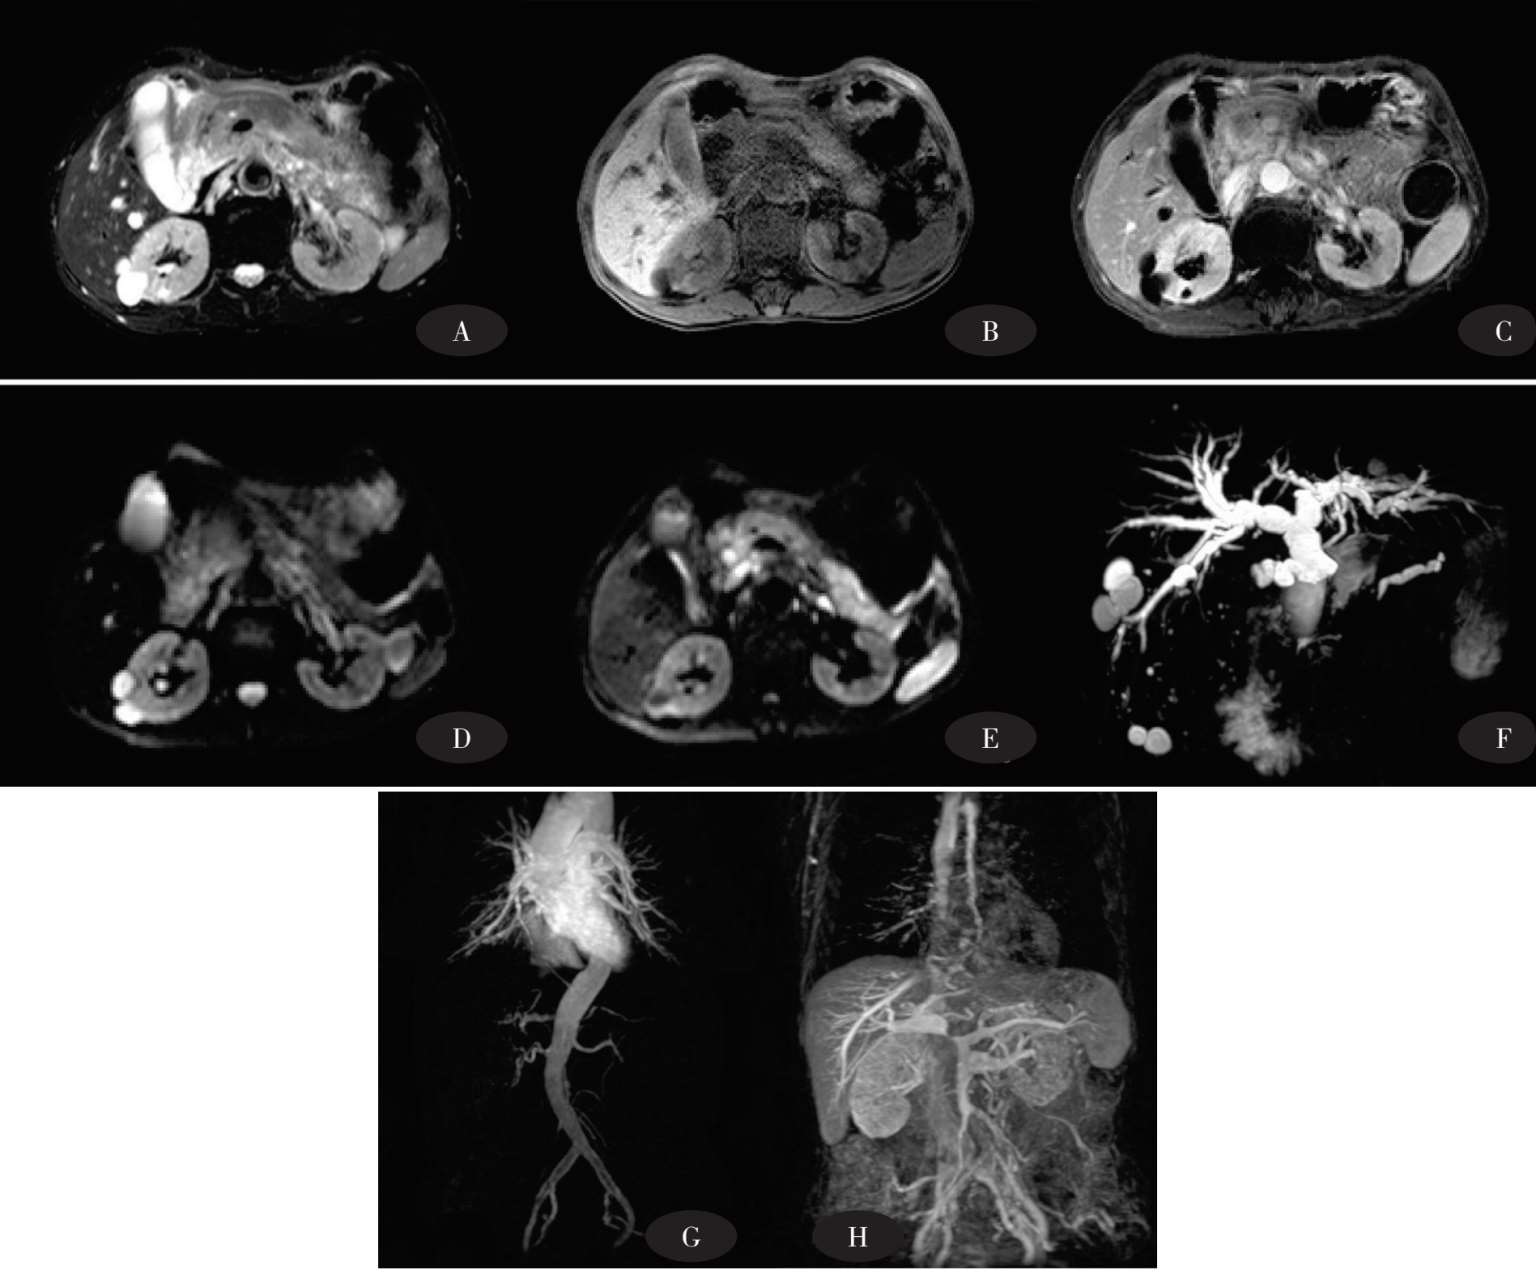

图8-2 胰腺癌影像

图8-3 胰腺癌影像,伴发肝内转移

图8-2A、图8-3A平扫期:胰体尾正常形态消失,呈局限性增大,病灶平扫呈不均匀低密度改变,边界较清楚;图8-2B:病灶强化不明显,在周围正常强化胰腺实质对比下呈不均匀低密度,胰周动脉强化,其中图8-2B显示病灶包容肠系膜上动脉及脾动脉;图8-2C门静脉期:病灶边缘呈轻度不均匀强化,与周围胰腺实质相比仍呈低强化,门静脉、肠系膜上静脉及脾静脉强化;图8-2D延迟期:病灶仍呈低强化。

图8-3显示肝内转移。图8-3A平扫期:肝内转移灶呈低密度;图8-3B动脉期:病灶中央强化不明显,边缘似呈轻度环形强化;图8-3C、图8-3D门静脉期+延迟期:肝实质明显强化,与肝内转移灶密度产生明显对比。

图8-4 正常胰腺MRI平扫+增强

图8-4A、图8-4B FSE-T2WI-FS:正常胰腺信号较同层面肝脏稍高,轮廓光滑,边界清楚,走行迂曲;胰管呈高信号纤细管道影。图8-4C、图8-4D FLASH-T1WI-FS:正常胰腺与同层面肝脏相比呈等信号或稍高信号;胰管呈低信号纤细管道影。图8-4E T1WI-FS增强期:胰腺呈均匀强化,强化程度接近同层面肝实质。图8-4F MRCP:肝内胆管及肝外胆管呈均匀高信号,胆管走行迂曲,边缘光滑,微细胆管显示欠佳;胃肠道黏膜呈高信号。

图8-5 胰头癌MRI平扫+增强+DWI+MRCP+MRA

图8-5A FSE-T2WI-FS:病灶呈不均匀高信号改变,边界不清。图8-5B FLASH-T1WI-FS:病灶呈不均匀低信号改变,胰管扩张呈低信号。图8-5C FLASH-T1WI-FS+C:病灶呈不均匀轻度强化。图8-5D、图8-5E DWI:病灶呈明显弥散受限,边界不清。图8-5F MRCP:肝内胆管及肝外胆管明显扩张,呈“软藤征”改变。胰管扩张,与扩张胆总管呈“双管征”改变;图8-5G、图8-5H MRA:门脉明确受侵、缩窄。